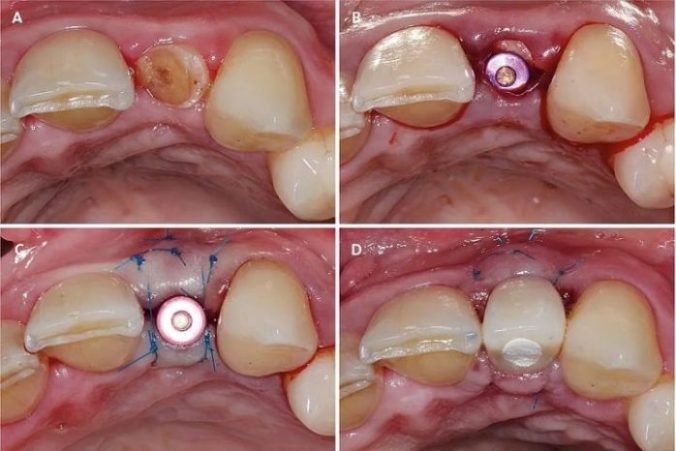

دکتر مهدی سمیعی ، جراح برجسته ایمپلنت دندان، با بهرهگیری از جدیدترین تکنولوژیها و متدهای علمی، فرآیند ایمپلنت را به شیوهای کارآمد و ایمن انجام میدهد. او با ارزیابی دقیق شرایط دهان و دندان بیماران، برنامهریزی شخصی سازی شدهای را برای هر فرد تدوین میکند. تکنیکهای پیشرفتهای که دکتر سمیعی به کار میگیرد شامل استفاده از تصویربرداری سهبعدی برای تحلیل ساختار استخوان و بافتهای نرم، و همچنین بکارگیری ایمپلنتهای با کیفیت بالا و سازگار با بدن انسان است. این رویکردها به کاهش عوارض و تسریع در روند بهبودی کمک میکنند.

در مرحله عمل، دکتر سمیعی با دقت و مهارت بالا، ایمپلنت را در محل مناسب قرار میدهد و تمامی مراحل را با رعایت اصول بهداشتی و استانداردهای بینالمللی انجام میدهد. او پس از نصب ایمپلنت، مراحل بعدی درمان را تحت نظر دارد و به بیماران مشاورههای لازم را برای مراقبت و نگهداری از ایمپلنتهای دندانی ارائه میدهد. این رویکرد جامع و حرفهای، حس آرامش و اعتماد را در بیماران ایجاد کرده و به آنها کمک میکند تا دوباره لبخند زیبا و سالمی را تجربه کنند.

ایمپلنت دندان یک فرآیند دقیق و حساس است که توسط دکتر مهدی سمیعی ، متخصص ایمپلنت دندان، با رعایت اصول علمی و حرفهای انجام میشود. در ابتدا، بیمار تحت بررسیهای جامع قرار میگیرد تا وضعیت سلامت دهان و دندان او به طور کامل ارزیابی شود. پس از این مرحله، برنامهریزی دقیق برای کاشت ایمپلنت صورت میگیرد و با استفاده از تکنولوژیهای پیشرفته، محل دقیق قرارگیری ایمپلنت تعیین میشود. این مرحله شامل تصویربرداری های پیشرفته و مشاوره با بیمار به منظور انتخاب بهترین گزینه برای نیازهای او است.

در مرحلهای که نوبت به جراحی میرسد، دکتر سمیعی با دقت و مهارت بالا، ایمپلنت را در استخوان فک قرار میدهد. این فرایند ممکن است با بیحسی موضعی یا بیهوشی عمومی انجام شود تا بیمار در طول عمل احساس راحتی کند. پس از قرارگیری ایمپلنت، دوره بهبودی آغاز میشود که در آن استخوان فک به تدریج با ایمپلنت جوش میخورد و استحکام لازم را به آن میبخشد. در نهایت، با قرار دادن روکش دندان بر روی ایمپلنت، بیمار میتواند لبخندی زیبا و طبیعی را دوباره تجربه کند و به زندگی روزمره خود بازگردد.